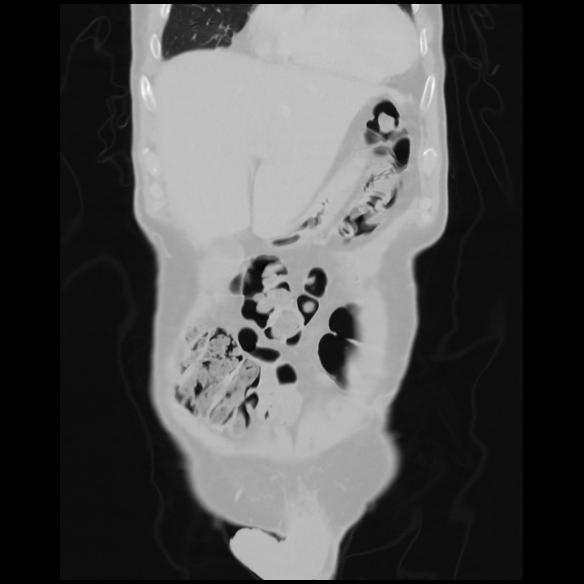

6 CUERPO,CE,Coronal,3.000,CUERPO,Coronal,